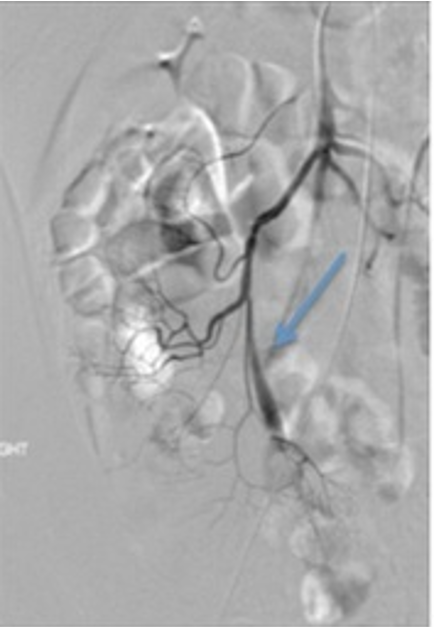

Vitelline artery (blue arrow)

angiography shows a prominent vitelline artery

Meckel’s diverticula are a persistent outpouching due to periistent non involuting omphalomesenteric (vitelline) duct. 50% contain gastric mucosa